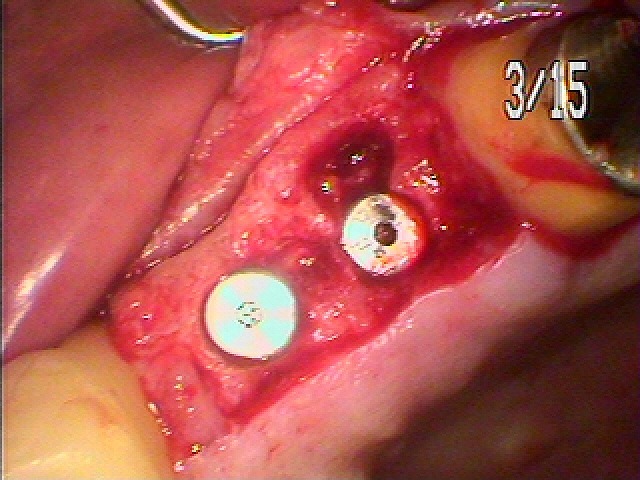

左上インプラント埋入。 2本埋入。| |広島市安佐南区の歯科医院 左上インプラント埋入。 2本埋入。 トップ お知らせ・ブログ 左上インプラント埋入。 2本埋入。 左上インプラント埋入。 2本埋入。 Web診療予約 初めての方へ 選ばれ続ける理由 院内設備について 歯が痛いしみる一般歯科 歯がぐらぐらする歯周病 健康な歯を保ちたい予防歯科 子供の虫歯予防をしたい小児歯科 銀歯をセラミックに審美歯科 白い歯を目指しませんか?ホワイトニング 矯正専門医がいるので安心矯正歯科 抜けた歯を補いたいインプラント・入れ歯 医院案内 スタッフ紹介 メリィハウス歯科クリニックオフィシャルホームページ ラベンダー歯科クリニックオフィシャルホームページ お知らせ・ブログ ホーム 診療科目 一般歯科 歯周病治療 予防治療 小児歯科 審美治療 ホワイトニング 矯正歯科 入れ歯・インプラント マウスピース矯正 初めての方へ 院長・スタッフ 設備紹介 医院案内・アクセス メニューを閉じる